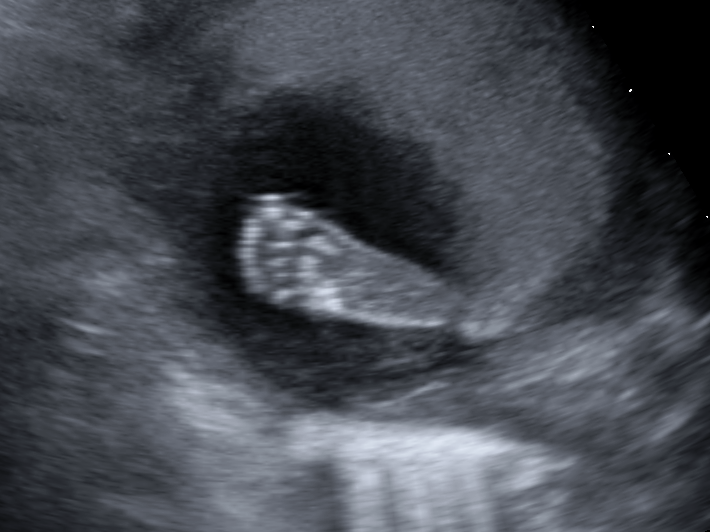

7 Weeks

At Approximately 7 weeks after the 1st day of the last menstrual period we will see a small fetus with a heartbeat in the gestation sac.